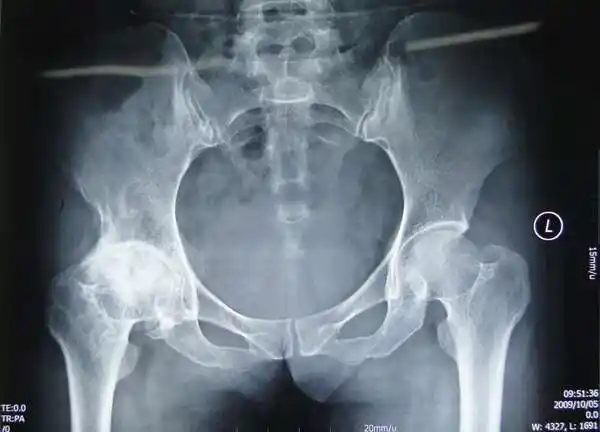

髋关节骨性关节炎人工全髋关节置换